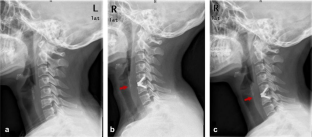

Fig. 3